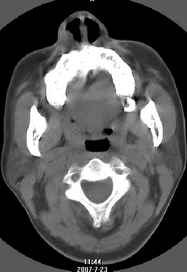

以下是引用还珠格格在2007-7-31 19:32:00的发言:[br]右侧鼻前庭内可见软组织块影,部分鼻中隔包绕其内,邻近骨质未见明显吸收破坏,考虑 1、鼻息肉可能性大 内翻乳头状廇不除外。期待结果。

以下是引用zjzjr在2007-7-31 20:29:00的发言:[br]右侧鼻前庭内可见软组织块影,部分鼻中隔包绕其内,邻近骨质未见明显吸收破坏,考虑 1、鼻息肉可能性大 内翻乳头状廇及肉芽肿类病变除外。期待结果。